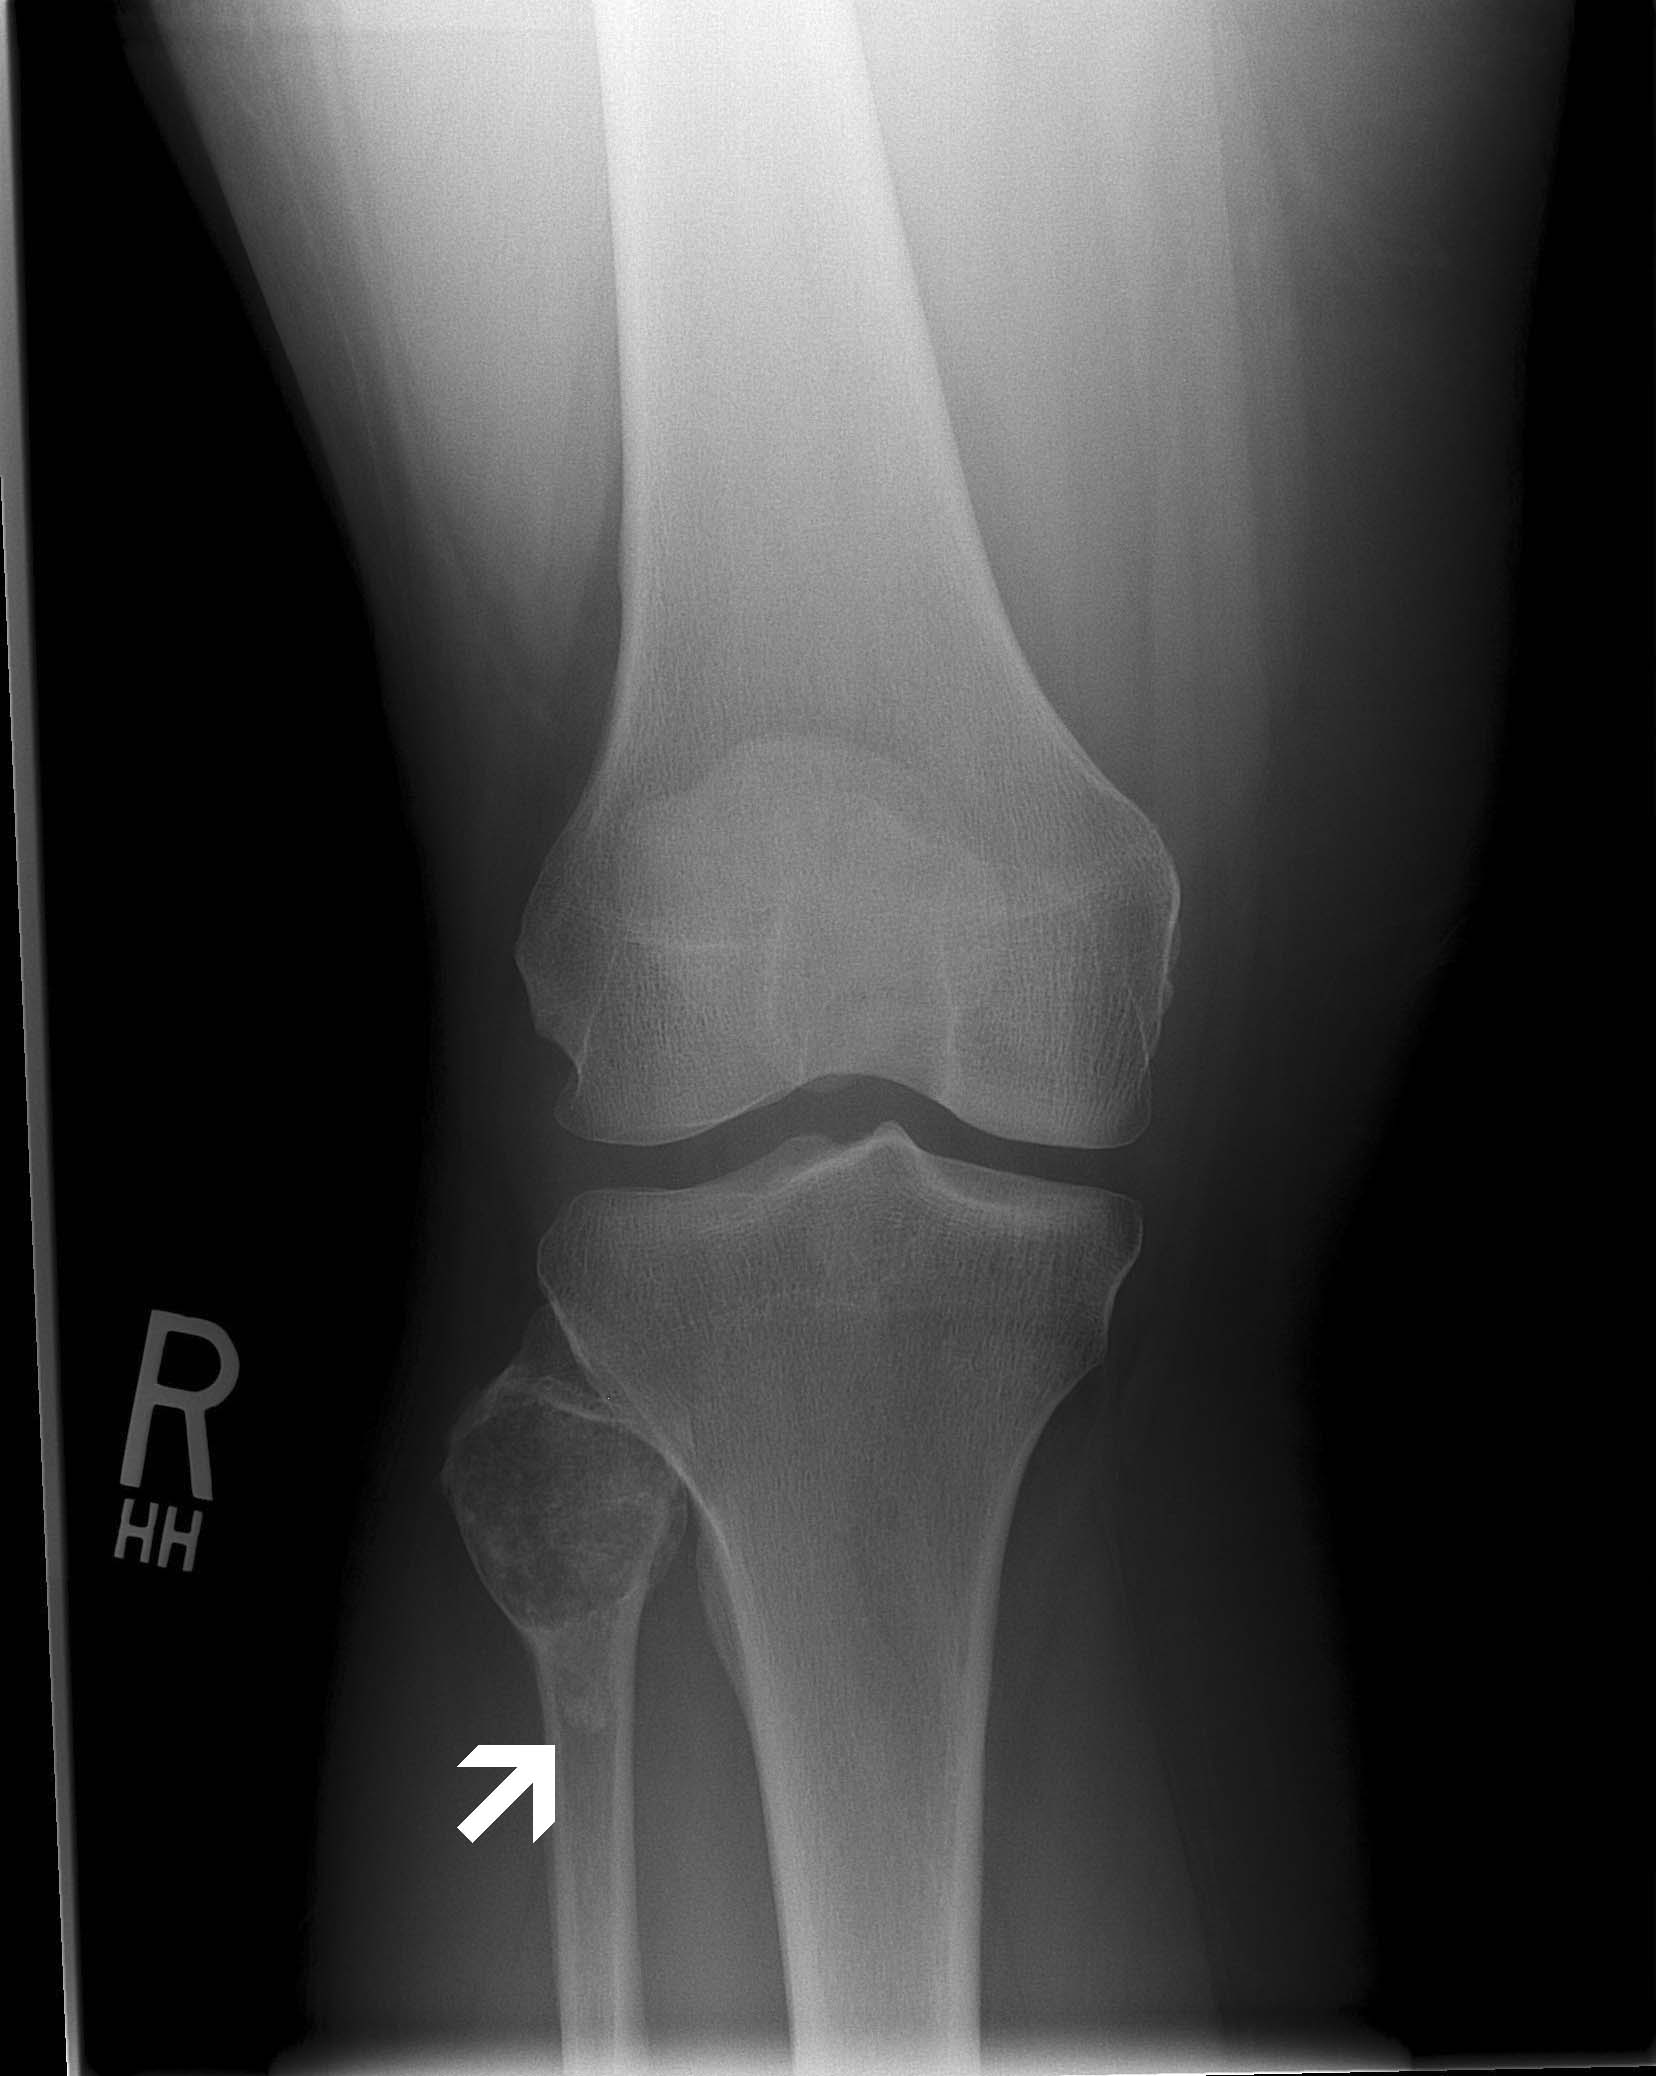

Plain Film:

Note the extension of the osteolytic lesion (arrow) towards the

diaphysis. |

- In this particular case there is

extension of the osteolytic lesion (arrow)

towards the diaphysis highly

suggestive of aggressive behavior. On the CT scan, the cortex